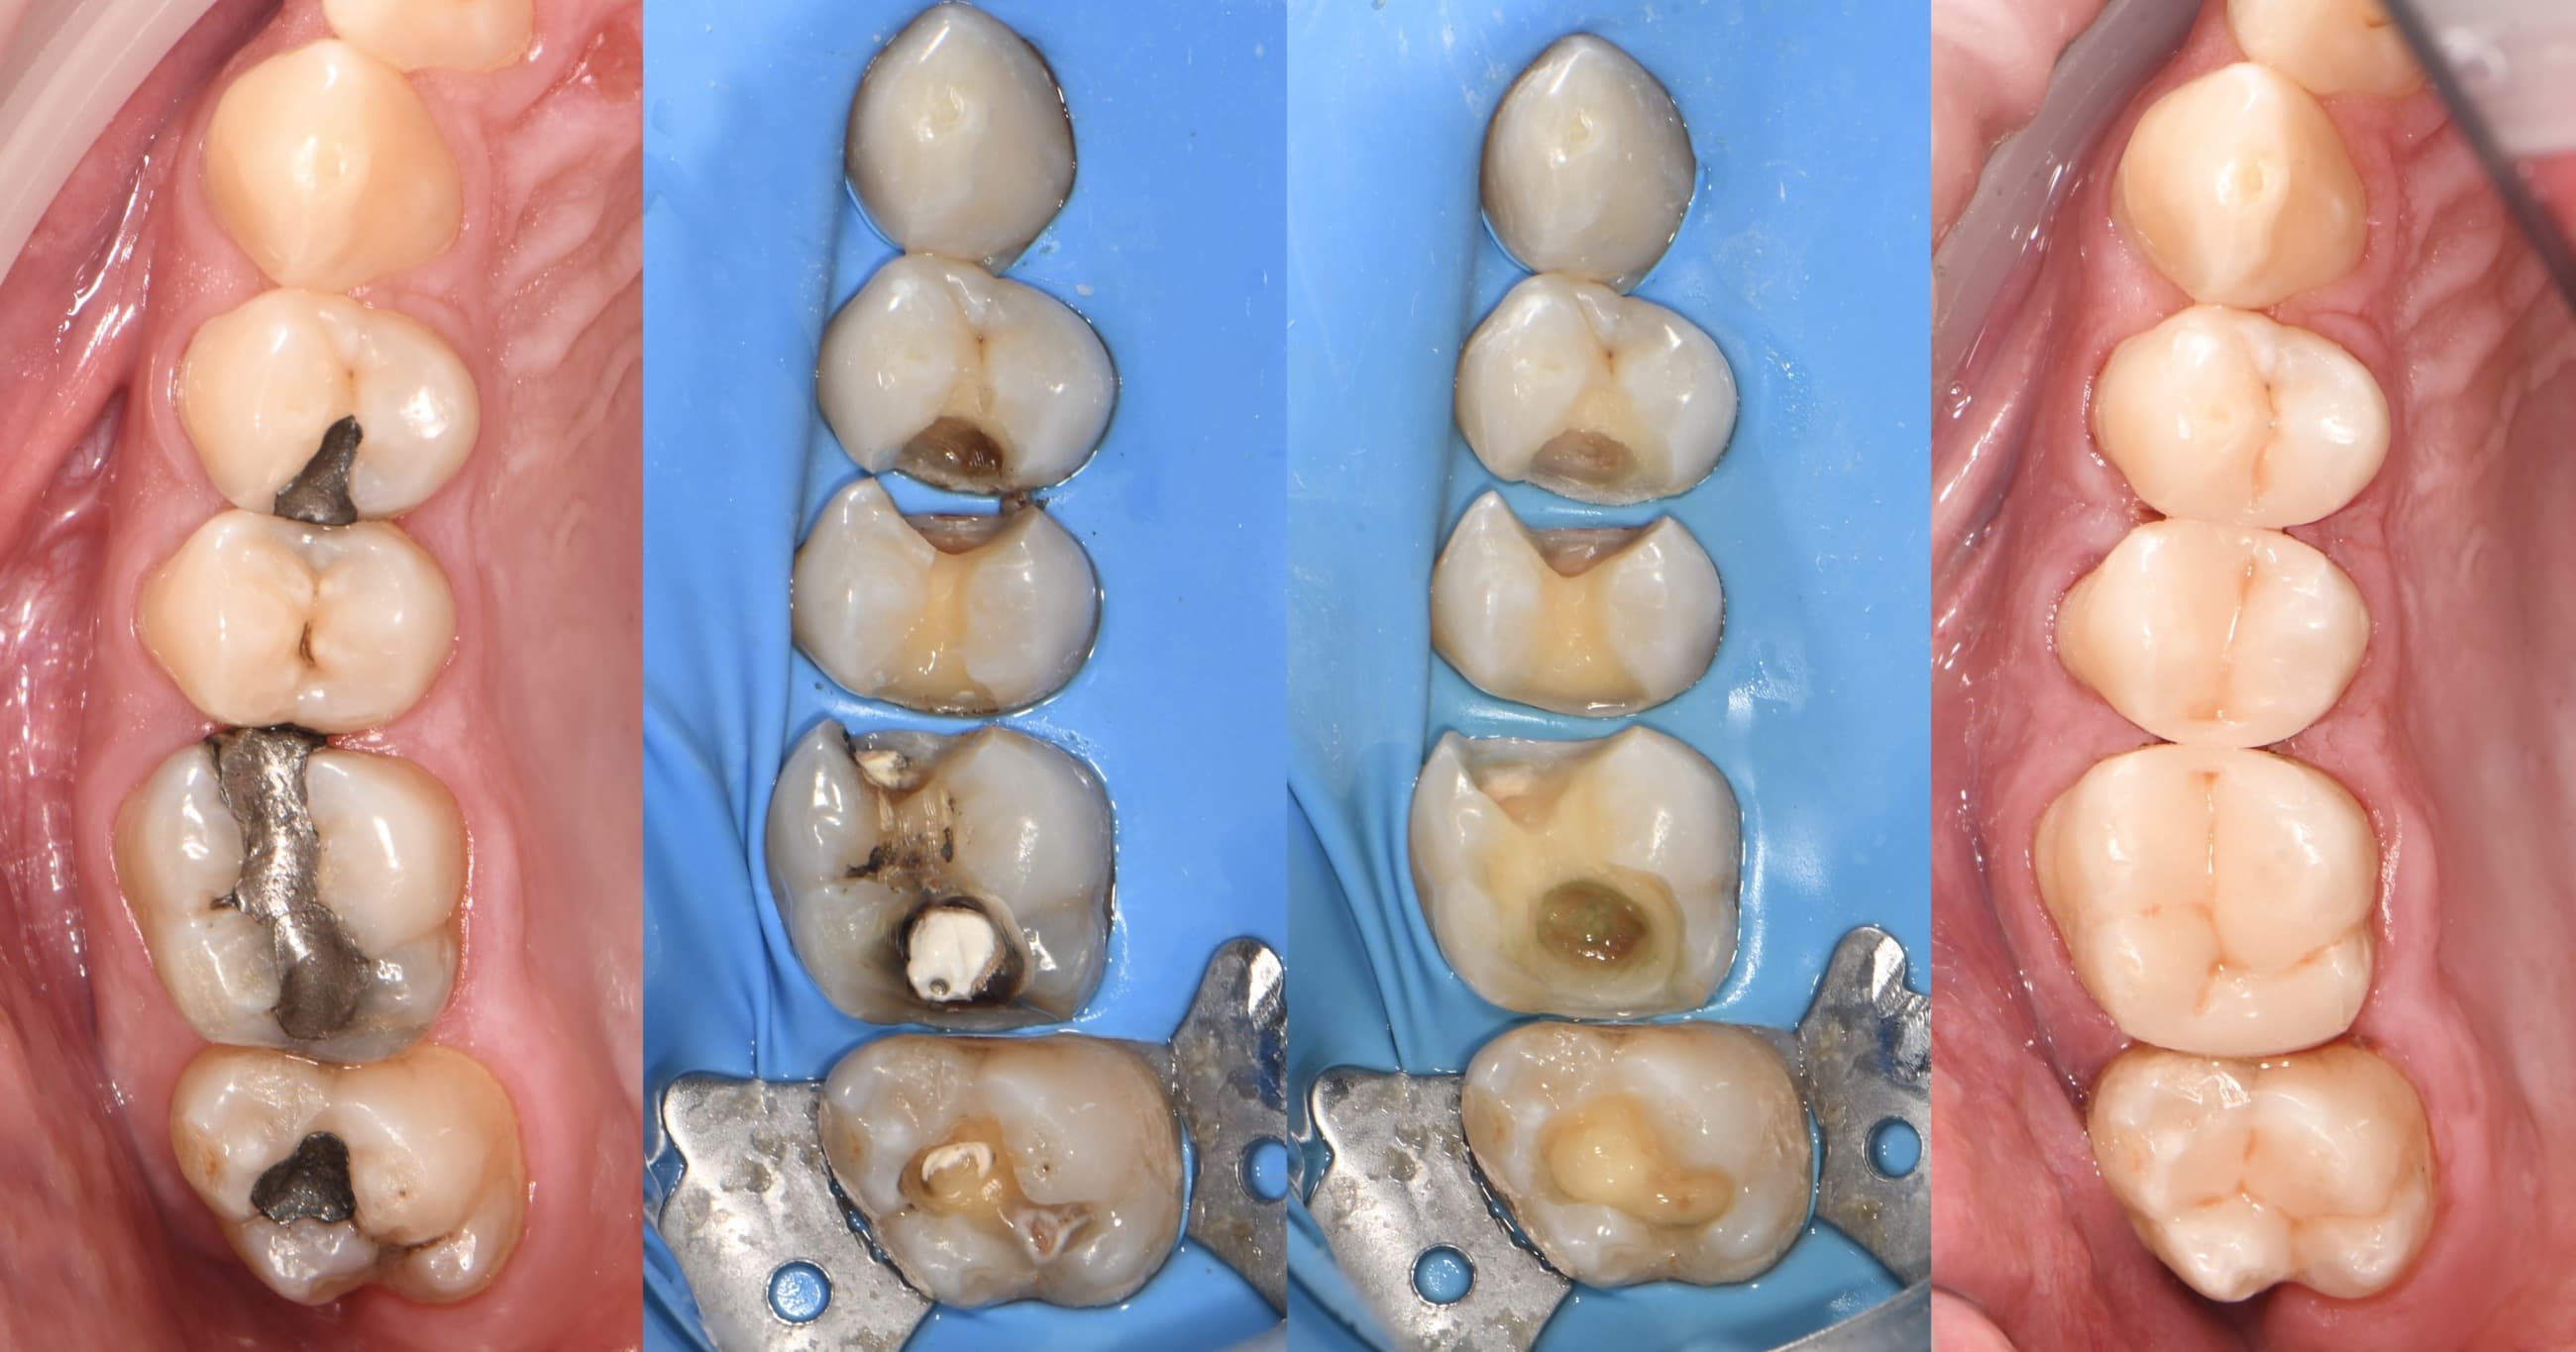

Výměna selhávajicích výplní na zubech 46 , 47 (dole vpravo)

Výměna podkažených starých kompozitních výplní na zubech 36 , 37 (dole vlevo)

Ošetření kořenových kanálků zubu 24 (nahoře vlevo)

Ošetření kořenových kanálků zubu 16 (nahoře vpravo)